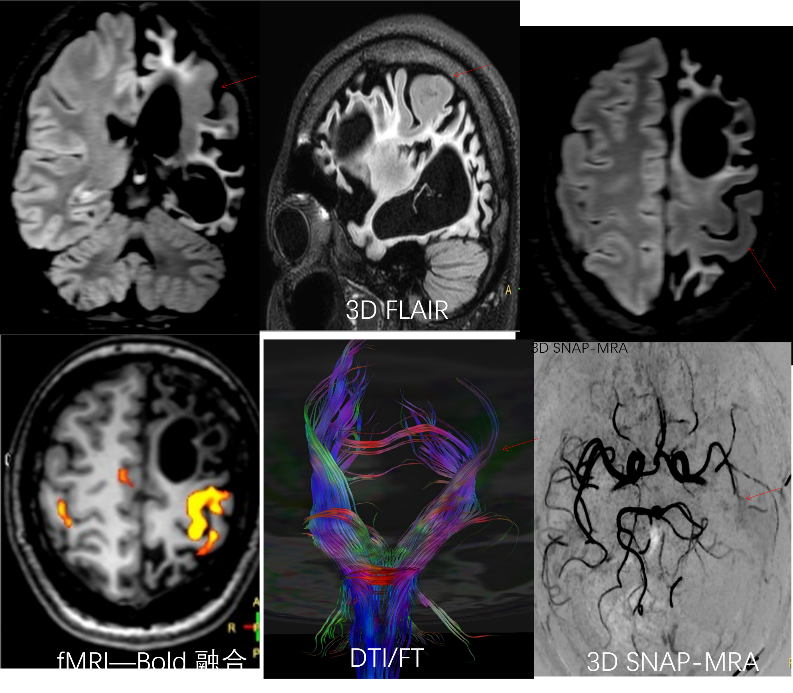

大脑结构 大脑血管及神经纤维束

脑膜瘤患者,手术前计划,通过高分辨脑表面血管与瘤体病变,脑整体结构融合,获得明确定位表征信息。 脑中线视神经乳头胶质瘤,高分辨脑神经系统3D FLAIR成像技术显示视神经乳头胶质瘤的空间三维特征,DTI及纤维示踪后处理技术显示与手术入路相关穹隆及视路神经纤维束走行及特征。

高分辨脑神经系统3D FLAIR成像技术显示局灶性皮质结构发育不良 高分辨脑神经系统mult-shot DWI 与传统single-shot成像技术对比,在脑灰质异位与急性脑皮质梗塞显示中更具优势。 3D SNAP-MRA 显示左大脑中动脉血管中断,3D FLAIR显示左脑萎缩及有功能的左手功能区,fMRI-Bold融合清晰显示功能区,DTI/FT 显示有功能的皮质纤维束。